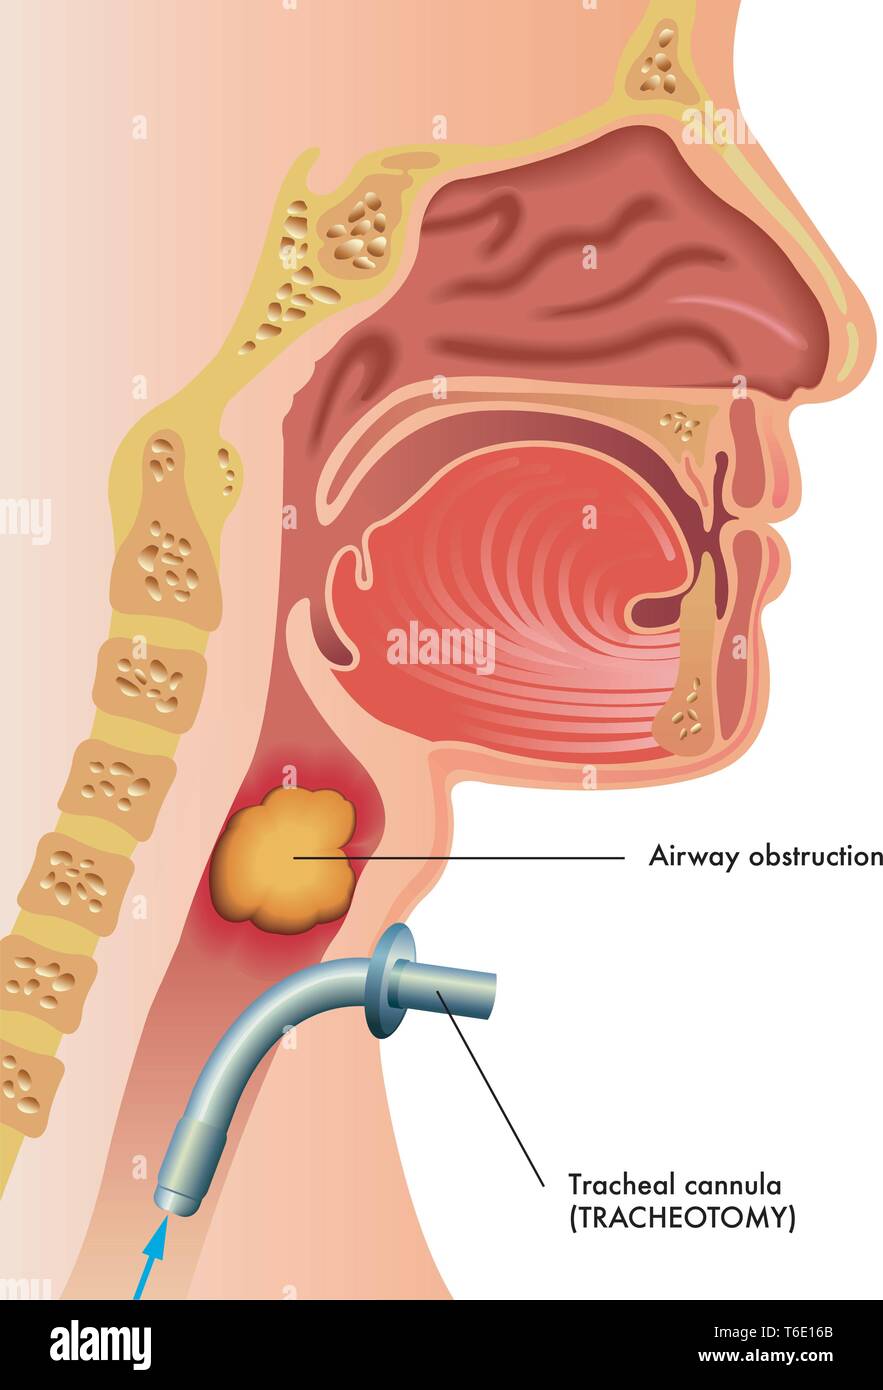

Medical illustration of a surgical tracheotomy Stock Vectorhttps://www.alamy.com/image-license-details/?v=1https://www.alamy.com/medical-illustration-of-a-surgical-tracheotomy-image244941379.html

Medical illustration of a surgical tracheotomy Stock Vectorhttps://www.alamy.com/image-license-details/?v=1https://www.alamy.com/medical-illustration-of-a-surgical-tracheotomy-image244941379.htmlRFT6E16B–Medical illustration of a surgical tracheotomy